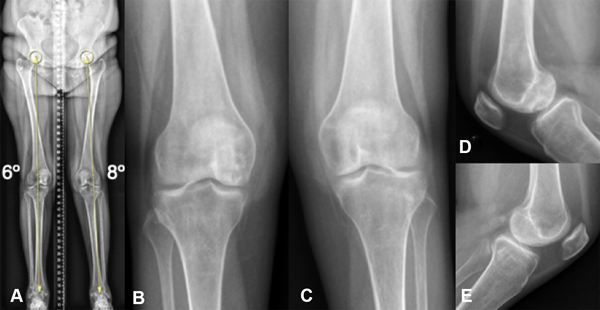

En la evaluación radiográfica se observaba un eje ligeramente valgo, de 6º en el miembro inferior izquierdo y un eje neutro con 8º en el derecho (fig. 1A), con incipientes signos de pinzamiento articular medial bilateral. Se veía una imagen radiolúcida, de contornos escleróticos proyectada en la superficie del cóndilo interno de la rodilla derecha, junto a una rarefacción ósea difusa del fémur distal y la tibia proximal bilateral (figs. 1B-C-D-E).

Figura 1: Radiografía de ambas rodillas. A) Escanograma frente, eje mecánico neutro. B) Rodilla derecha frente. C) Rodilla izquierda frente. D) Rodilla derecha perfil con imagen radiolúcida en la superficie del cóndilo interno, junto a rarefacción ósea difusa. E) Rodilla izquierda perfil con rarefacción ósea difusa.